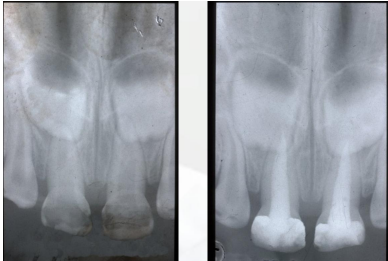

ENDODONZIA PEDIATRICA

In caso di carie profonde che coinvolgono la polpa dentale, interveniamo con l’endodonzia pediatrica. Presso il nostro studio di Bologna eseguiamo terapie canalari sui denti da latte e sui denti permanenti giovani, con l’obiettivo di preservare il dente e la sua funzione. Utilizziamo materiali e tecniche specifiche per l’età pediatrica, garantendo sicurezza e comfort.